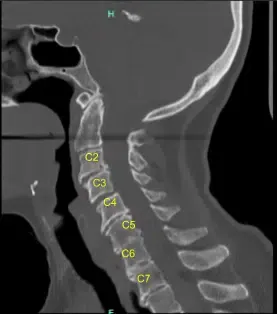

The CT scan was suggestive of Degenerative disc disease at multiple levels. The patient gave informed consent, understanding all of the risks, benefits, and alternatives to surgery. We discussed treatment options and agreed to go ahead with Anterior Cervical Discectomy and fusion C3 to C6.